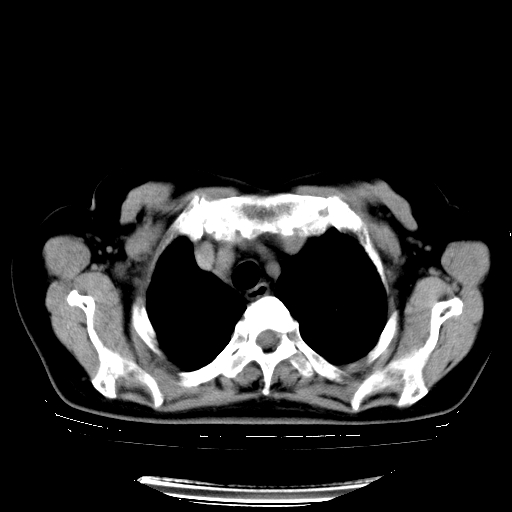

以下是引用zhangzhongshou在2008-3-22 12:52:00的发言:[br]1、右侧液气胸。[br]2、腹水。建议进一步检查。

以下是引用鲁巨ct在2008-3-22 14:10:00的发言:[br]1、右侧液气胸,右中下叶节段性不张。[br]2、腹水,建议上腹部ct检查

以下是引用zjzjr在2008-3-22 17:19:00的发言:[br]1、右侧液气胸,右下叶节段性不张。[br]2、腹水,建议上腹部ct检查